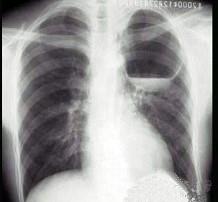

问题 男,26岁,胸闷伴胸痛,胸片如图,最可能的诊断为 ( )

选项 A.左上肺空洞型结核 B.左上肺脓肿 C.左上肺液气囊肿 D.左上肺包虫病 E.韦格肉芽肿

答案 C